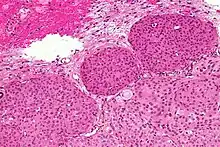

- A woven architectural pattern

- Psammoma bodies (spheroid calcifications)

- Syncytial cells (having indistinct cell membranes) with eosinophilic (pink) cytoplasms

- Round uniform nuclei

- Whorls (concentric cell arrangements)[16]

Meningiomas arise from arachnoidal cap cells,[17] most of which are near the vicinity of the venous sinuses, and this is the site of greatest prevalence for meningioma formation. Some subtypes may arise from the pial cap cells that migrate during the development together with blood vessels into the brain parenchyma.[18] They most frequently are attached to the dura over the superior parasagittal surface of frontal and parietal lobes, along the sphenoid ridge, in the olfactory grooves, the Sylvian region, superior cerebellum along the falx cerebri, cerebellopontine angle, and the spinal cord. The tumor is usually gray, well-circumscribed, and takes on the form of the space it occupies. They usually are dome-shaped, with the base lying on the dura.

Histologically, meningioma cells are relatively uniform, with a tendency to encircle one another, forming whorls and psammoma bodies (laminated calcific concretions).[19] As such, they also have a tendency to calcify and are highly vascularized.